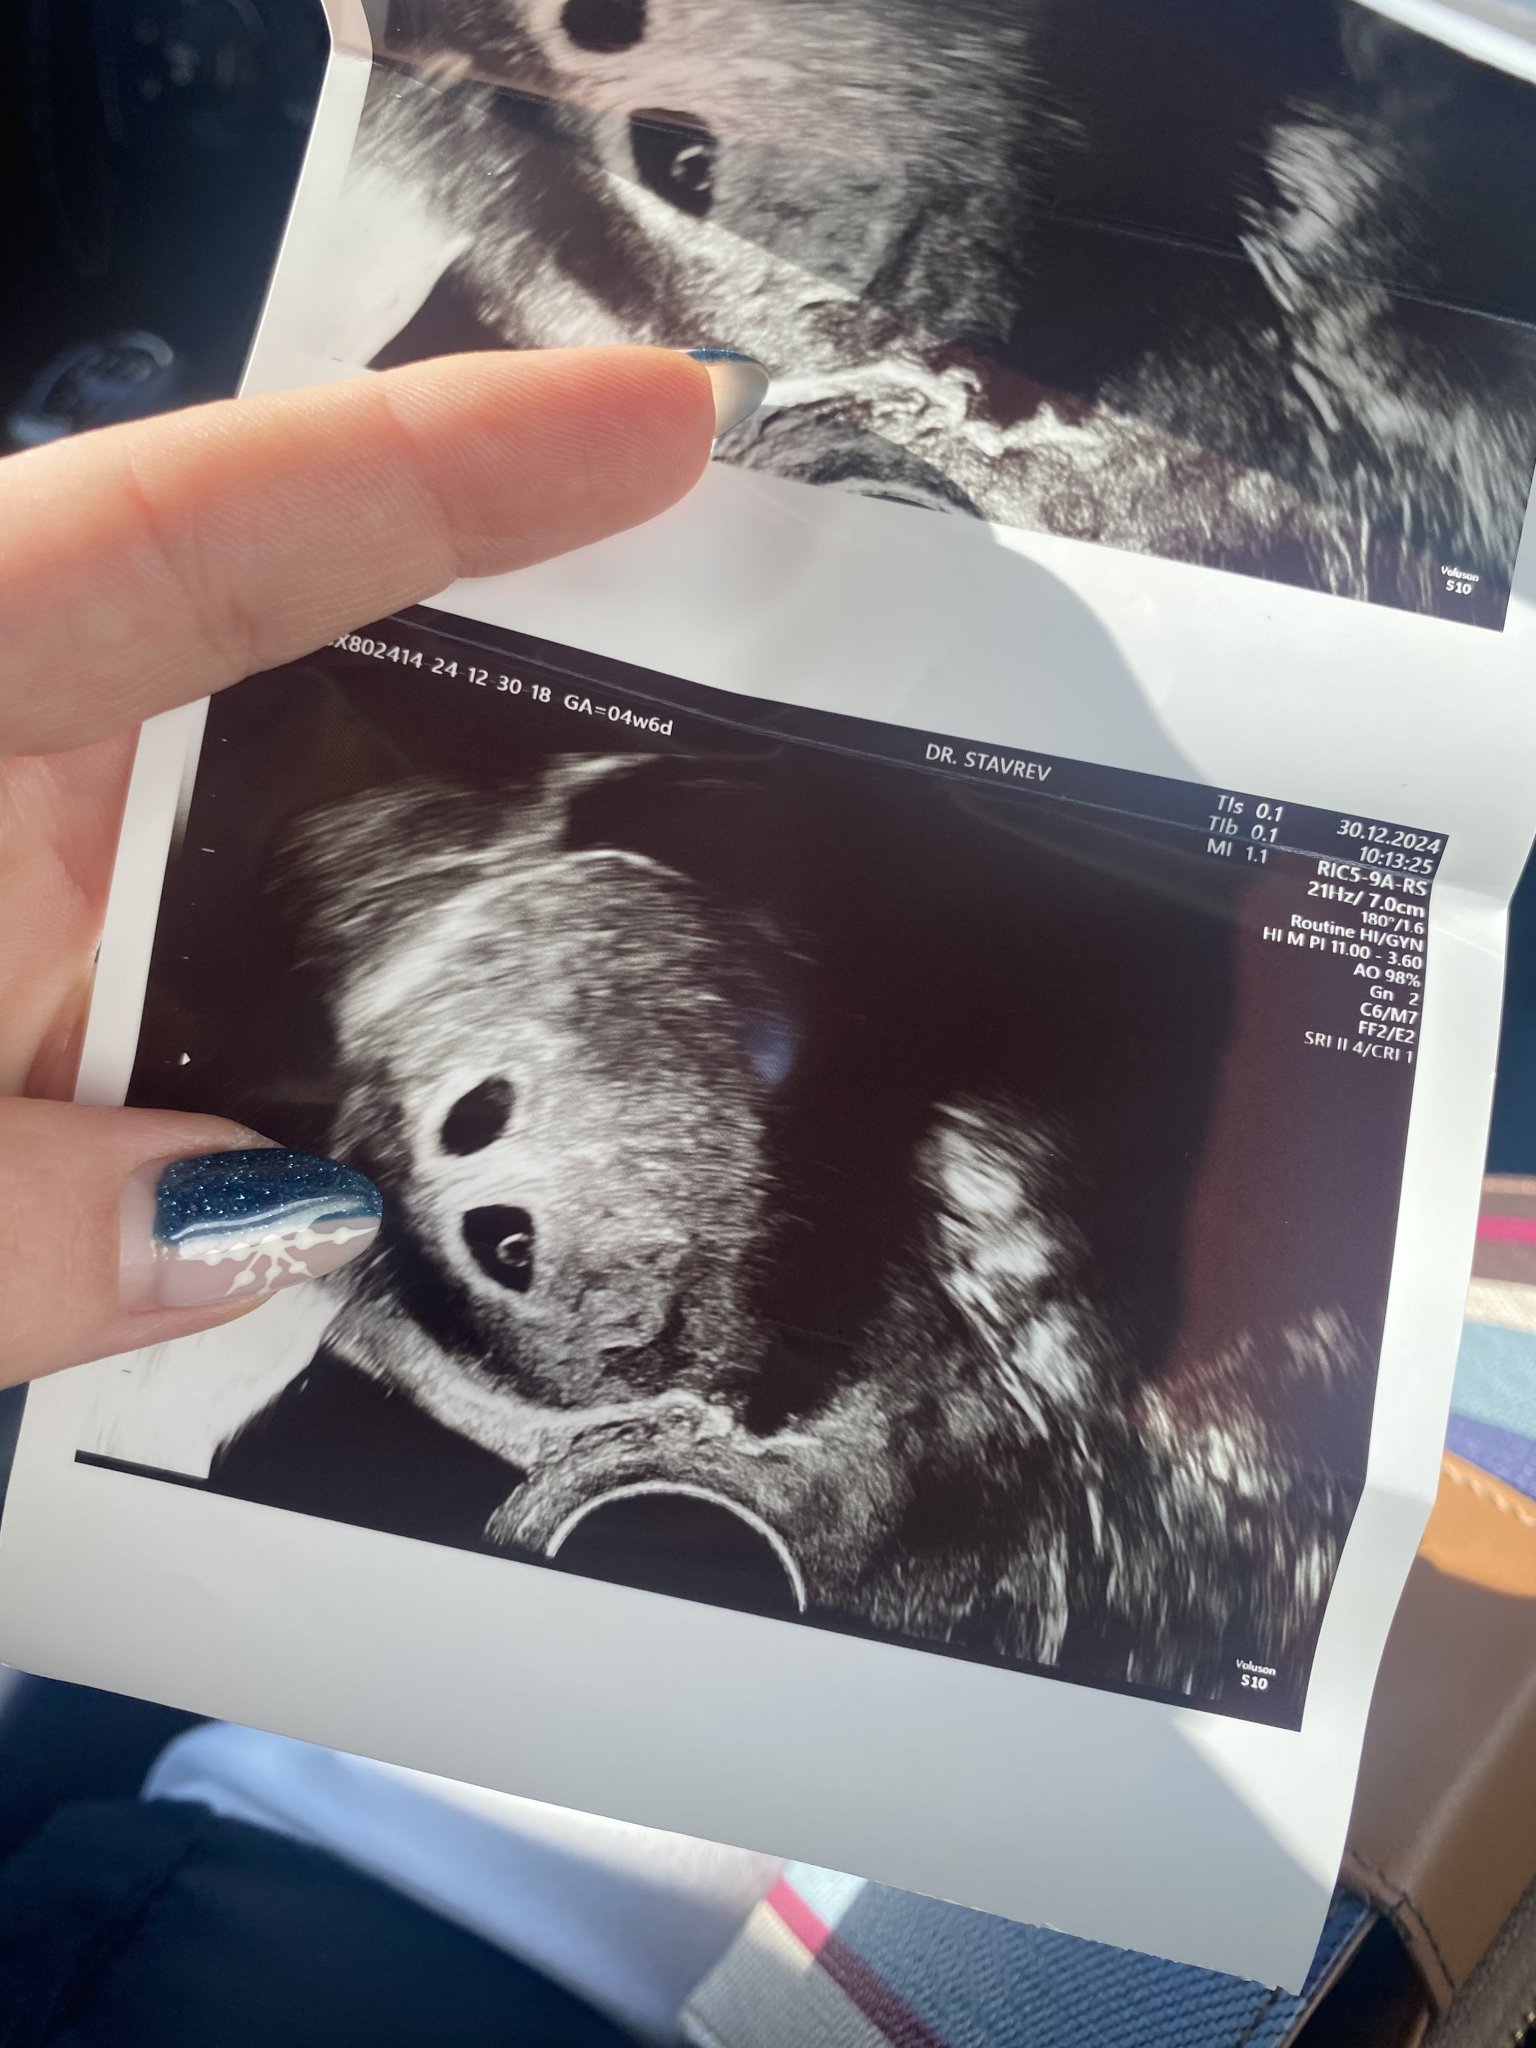

Здравейте,комичета днес бях на преглед след зет на два ембриона доктора каза, че всичко е наред 4та седмица и 6 дни. След прегледа нямах нищо сега имах кръв по салфетката кафяво с примеси на червено. Дали е нормално? Малко се притеснявам?

Мис с вагинален ехограф ли беше?

Дааа, доста си ме почовърка

нормално е да има леко прицапване